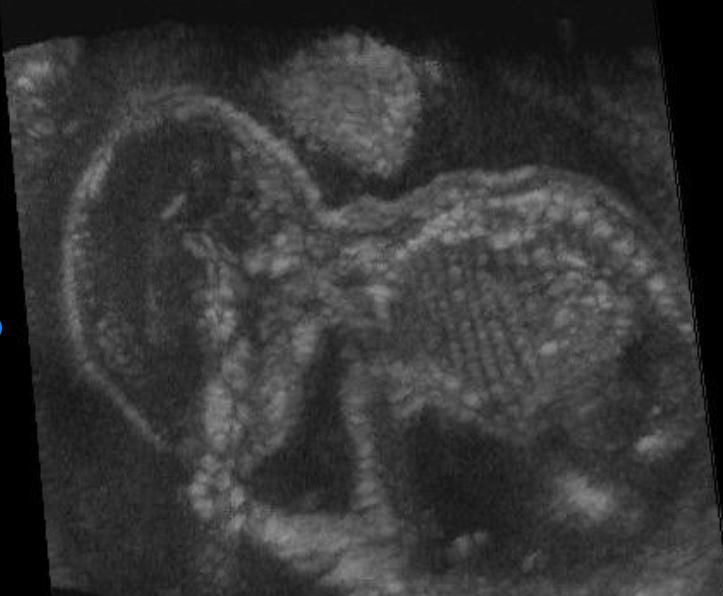

A scan of a foetus